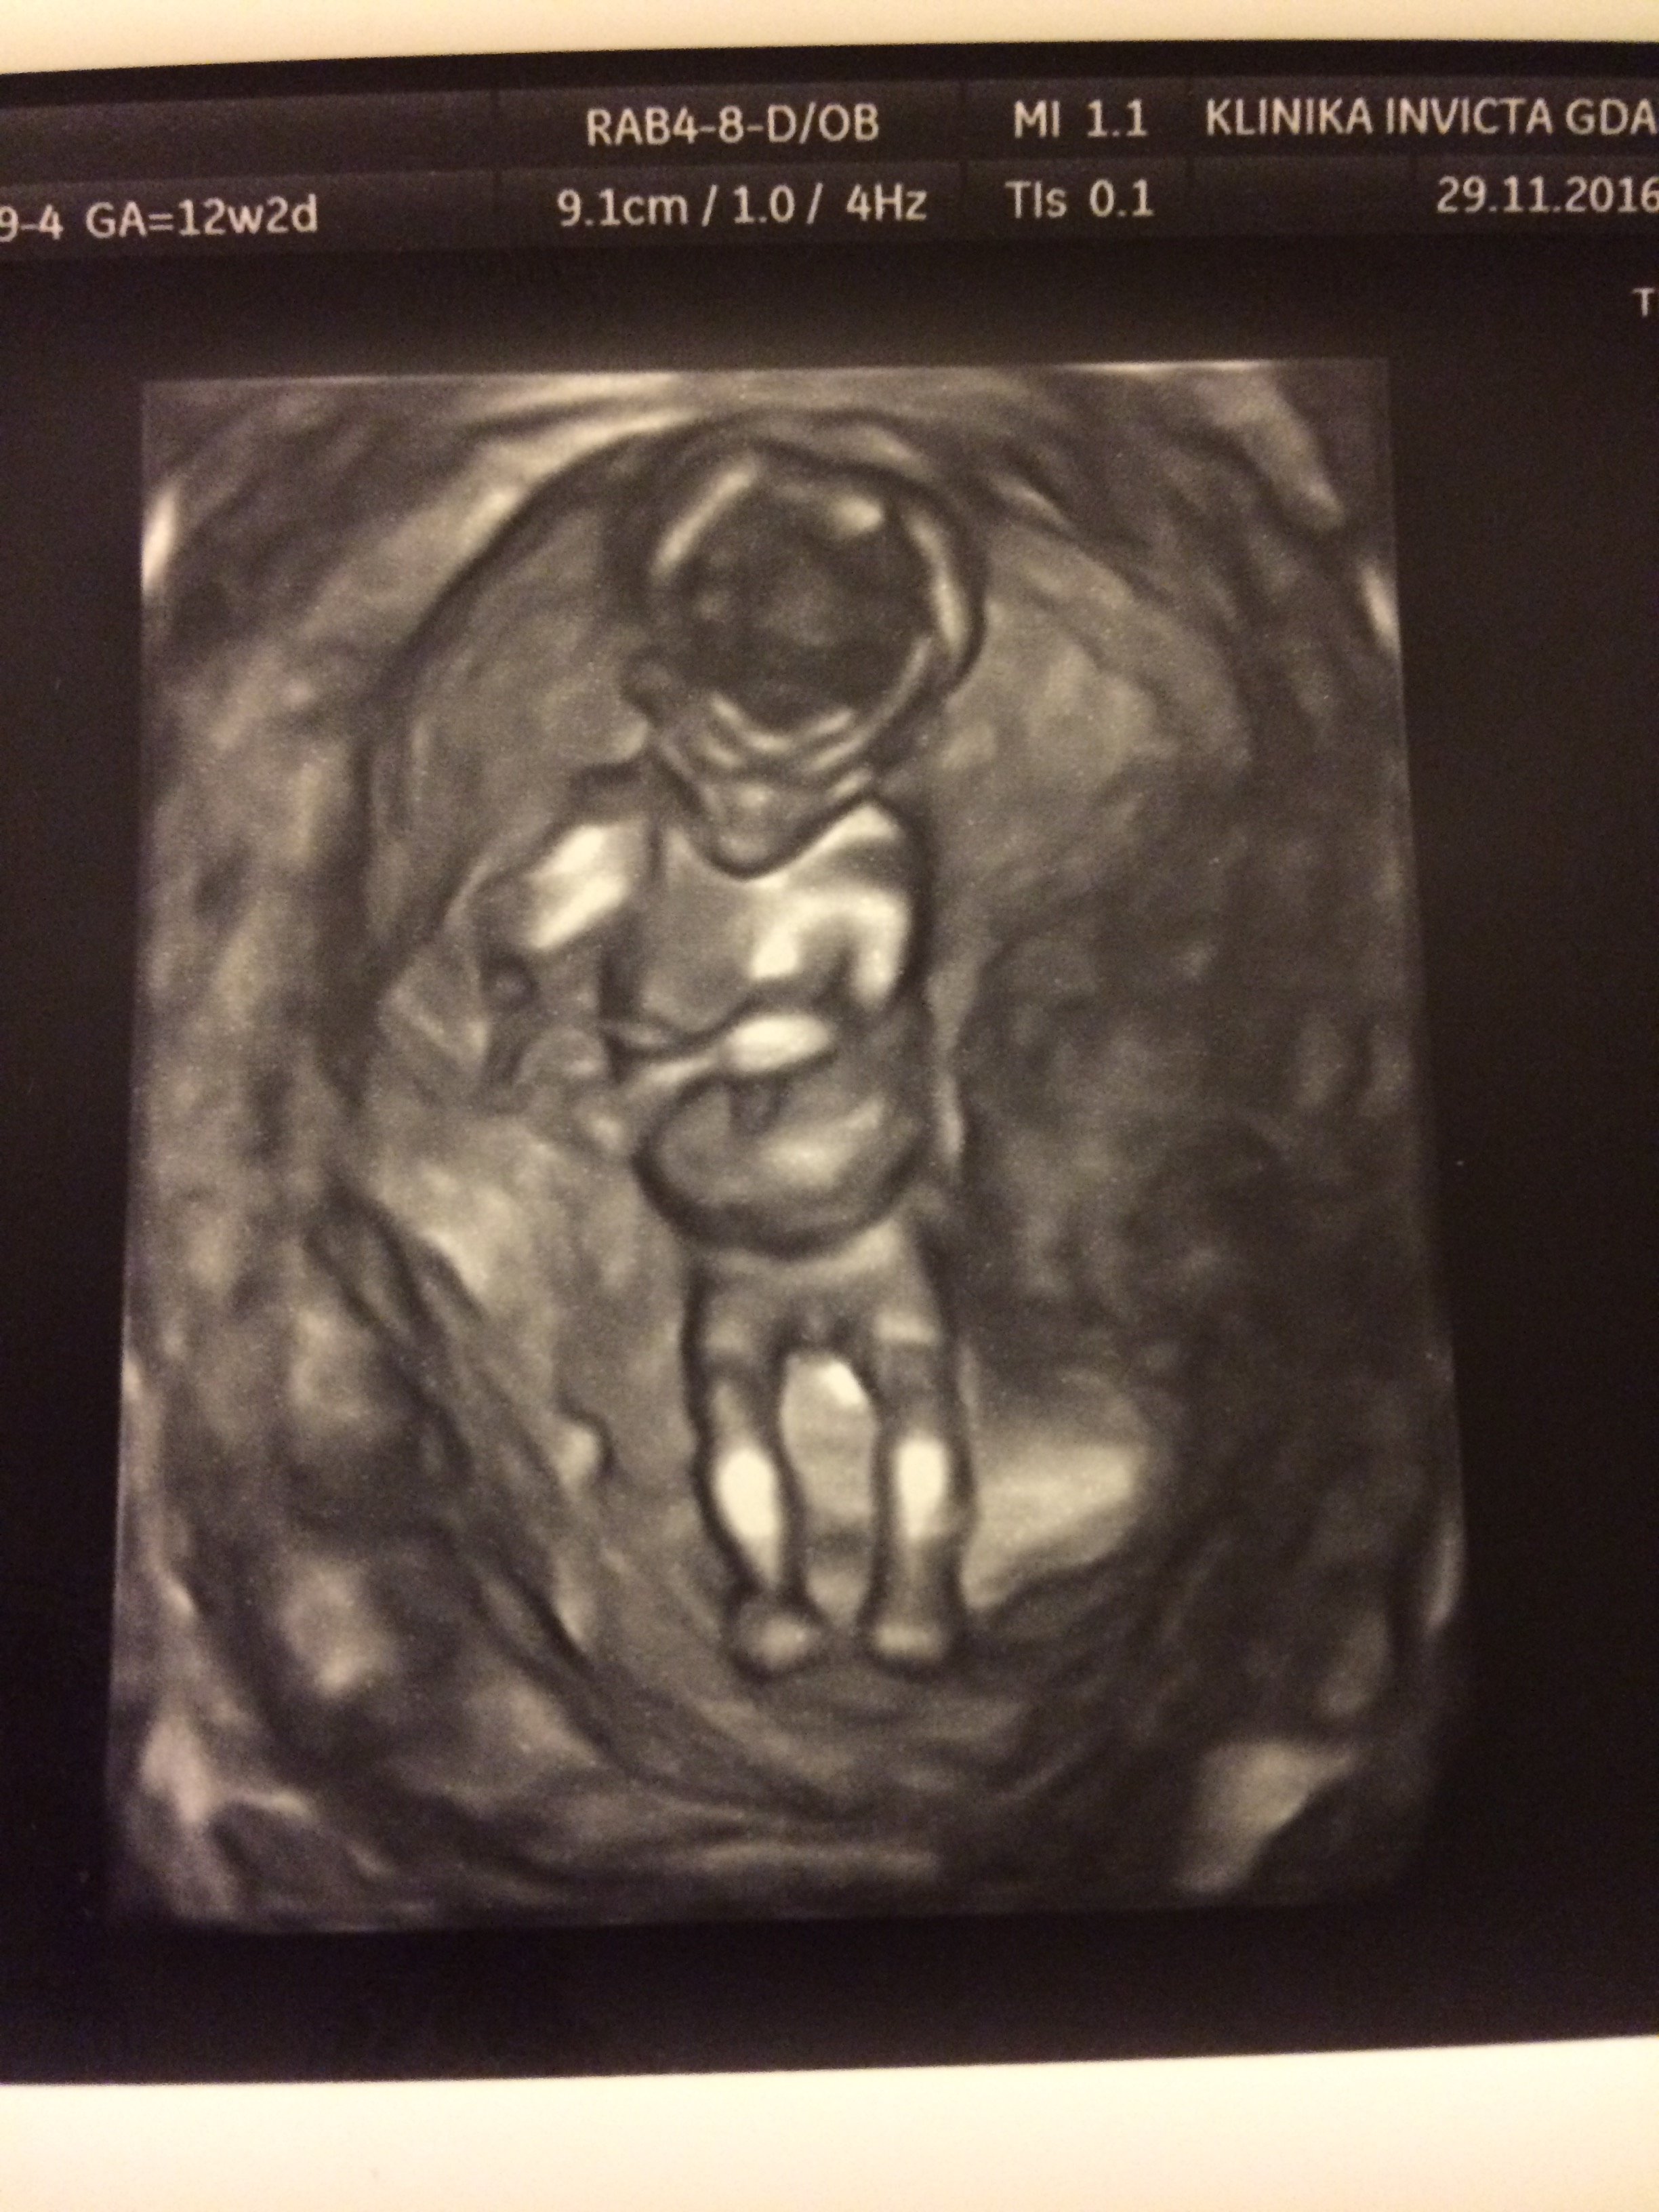

Dziś miałam z mężem dzień wolnego, bo nie tylko musieliśmy ogarnąć prezenty na Święta (nie robimy takich rzeczy na ostatnią chwilę by oszędzić sobie stresu), ale jechaliśmy do Gda na USG 1.trymestru! Prawdę mówiąc pomieszane były emocje ekscytacji z obawami, które chyba każda gdzieś tam ma. Niewiele rosnę, póki co poza mdłościami niewiele czuję... ale ciagle towarzyszy mi uczucie że jest tam ten mój Mały Ktoś

Nie zanudzając... obawy okazały się zbędne, a nasz Maluszek ma się cało i zdrowoPodczas badania uraczył nas ruszającym się nóżkami i rączkami. Magiczne uczucie

Całe 6,1cm Człowieka.

Zobacz załącznik 785485